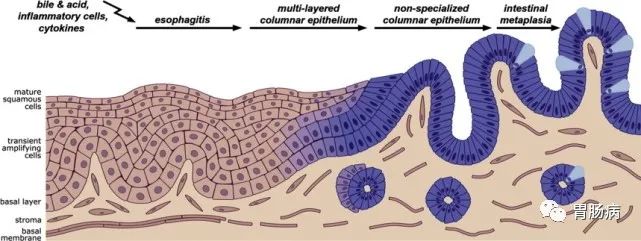

因为一般的肠型胃癌,是在胃粘膜上皮生长,胃镜进去,就一览无余,很容易发现;

而印戒细胞癌却是向胃壁外面生长,在早期,甚至在进展期,在胃粘膜表面并没有明显的改变,所以很容易漏诊。

我们的胃镜检查,就好比一个人进到屋子里观察室内的墙壁,但是壁纸下面、屋子外面的墙壁,却看不到,而这种癌就是隐藏在是墙纸下面,向外发展;

印戒细胞癌是一种组织类型,它拥有一个浪漫的名字,是根据其癌细胞在显微镜下的形态而得名,由于细胞含有大量黏液、胞质丰富、细胞核被挤压至胞质一侧,其形态呈“印戒”样,故得名。

癌细胞含有大量黏液、胞质丰富、细胞核被挤压至胞质一侧

胃印戒细胞癌被归类为弥漫型癌,属于未分化癌的一种(癌的病理学分类,分化越好,预后越好,比如高分化好于中分化和低分化,未分化最差)。